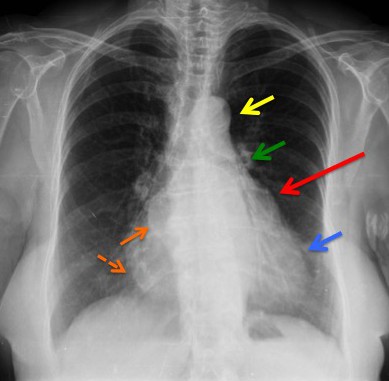

CASO: Disnea. Paciente con insuficiencia cardiaca.

Hallazgos:

- Cardiomegalia.

- Signo del 3º mogul y doble contorno por crecimiento de la aurícula izquierda.

- Bronquio izquierdo rectificado por crecimiento de la aurícula izquierda (signo de la bailarina).

- En la placa lateral, además se observa elongación aórtica.

- Parénquimas pulmonares sin hallazgos.

Signo del doble contorno: La AI aumentada de tamaño produce un segundo contorno que normalmente no debería figurar (flecha naranja contínua).

Flecha amarilla: cayado aórtico.

Flecha verde: arteria pulmonar.

Flecha azul: ventrículo izquierdo.

Signo del tercer mogul: se refiere a la lobulación anormal del contorno mediastínico izquierdo entre la arteria pulmonar y el ventrículo izquierdo. Pueden producir esta lobulación lesiones cardíacas y pericárdicas (orejuela izquierda aumentada, aneurisma ventricular o de la arteria coronaria, quiste o masa pericárdicos, etc) y también algunos tumores mediastínicos, como timomas. En la imagen, el signo corresponde al crecimiento de la orejuela izquierda (flecha roja). La palabra “mogul” es un término utilizado por los esquiadores para describir un acúmulo mamilar de nieve compacta en una ladera montañosa. El primer mogul corresponde al cayado aórtico (flecha amarilla); el segundo, a la prominencia de la arteria pulmonar (flecha verde); y el cuarto, al contorno del ventrículo izquierdo (flecha azul).

Signo del doble contorno: indicativo de crecimiento de la aurícula izquierda en la radiografía posteroanterior de tórax. La aurícula izquierda no forma parte normalmente del contorno cardiaco derecho en esta proyección; sin embargo, cuando aumenta de tamaño, produce un segundo contorno (flecha narana contínua), además del de la aurícula derecha (flecha naranja discontinua).

Signo de la bailarina: es un signo de crecimiento de la aurícula izquierda visible en la radiografía posteroanterior o anteroposterior de tórax, y consiste en el aumento del ángulo traqueal por levantamiento del bronquio principal izquierdo (flecha rosa). El nombre del signo se debe al parecido de la imagen con la apertura de piernas (spagat) de una bailarina.